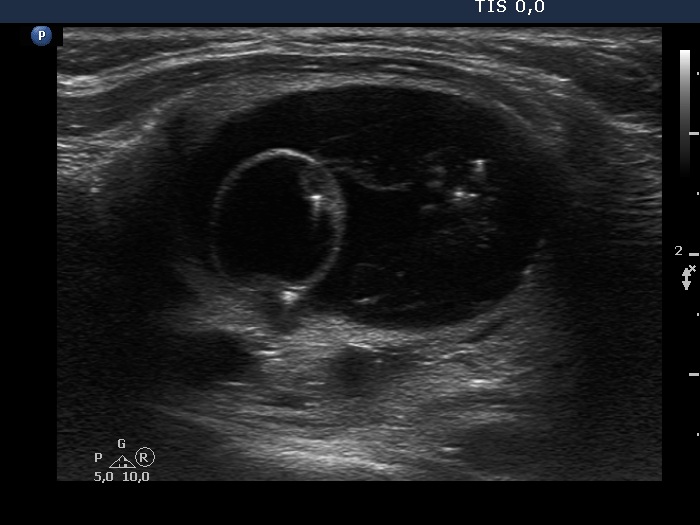

The composition of the nodule - case 1297 (ultrasonographic picture 4)

Left lobe, longitudinal scan. The unusual, ring-shaped part might correspond to the solid part which had undergone cystic degeneration.